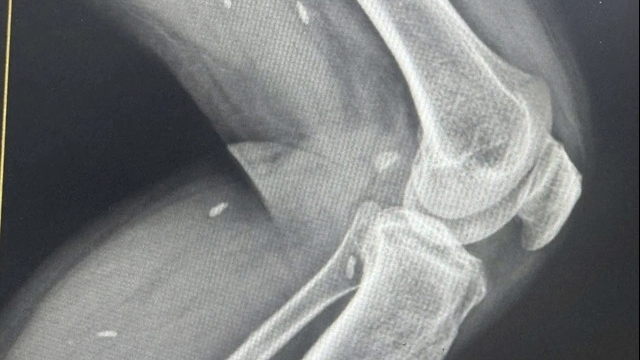

Bệnh án của một bệnh nhân có sự bất thường về thai sản. Ảnh: Dương Đình Tường.